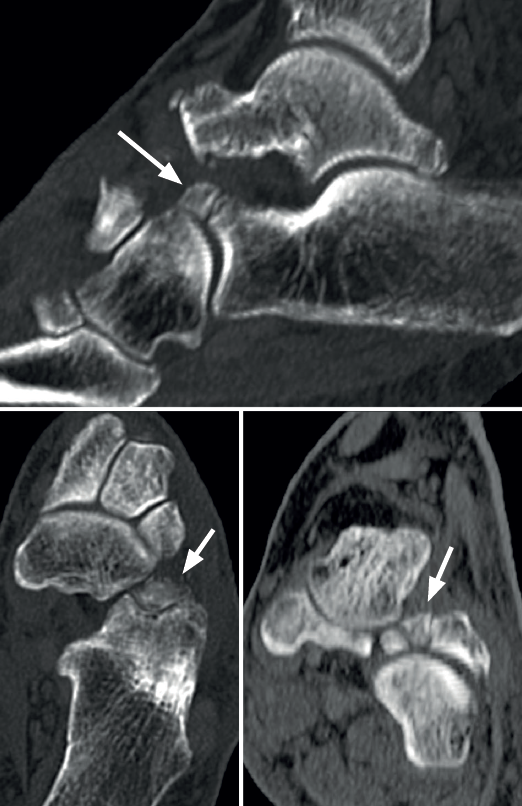

En la última década del siglo XIX nacieron dos teorías. Una de ellas, de Pfitzner en 1896, sugería que las coaliciones eran debidas a la presencia de osículos accesorios situados entre dos huesos del tarso y su posterior incorporación a ellos(10). Se dedujo por la frecuente aparición de esos osículos en las mismas zonas donde suelen presentarse las coaliciones. Muchos autores apoyaron esta teoría, pues encontraban un os sustentaculum proprium en el mismo sitio donde se producían con tanta frecuencia las coaliciones de la faceta media de la articulación subastragalina, así como un os calcaneus secundarium en las coaliciones entre calcáneo y escafoides (Figura 1) y también las de la carilla subastragalina posterior, donde se asienta habitualmente el os trigonum(11). Sin embargo, esa teoría fue refutada cuando en 1955 se demostraron coaliciones tempranas en fetos en los que no habría dado tiempo al desarrollo de los osículos y su incorporación a los huesos vecinos(12).

Rozansky(41) y Lim(42) propusieron, solo para la coalición AC, una clasificación basada en imágenes 3D de TC. Ambos se basaron en la morfología de inclinación de la interlínea y la naturaleza del tejido (fibrocartilaginoso u óseo), pero Lim añadió la presencia de fractura con edema óseo asociando criterios de RM. Yun(43) también hizo uso de la TC y la RM para describir diferentes tipos de coalición AC según su localización y la presencia o no del os sustentaculi, que se sitúa entre el borde más posterior del sustentaculum tali y la prominencia más posteromedial del astrágalo. Por último, Wang(44) ha propuesto una excelente clasificación para describir la morfología de la coalición, según el hueso protagonista (sobrecrecimiento del astrágalo o del calcáneo, de ambos o con osículo intermedio), en función también de su condición fibrocartilaginosa u ósea, así como de la afectación sea de la subastragalina media, la posterior o de ambas.